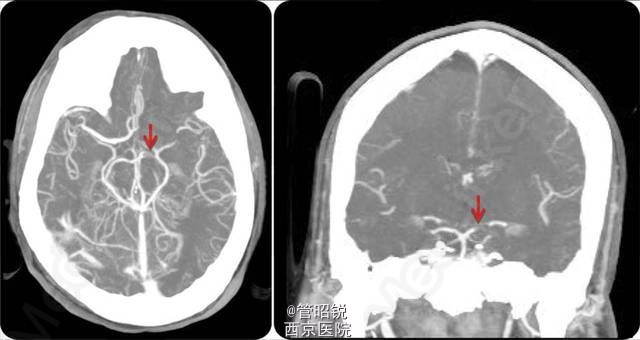

患者男性,38 岁,突发右侧肢体偏瘫、偏身感觉障碍及偏盲。头颅 CT 显示左侧大脑后动脉高密度征 (Hyperdense posterior cerebral artery sign,HPCAS)(见图 1)。CTA 显示左侧大脑后动脉闭塞(见图 2)。MRI 显示左侧大脑后动脉梗塞。经食管超声心动图检查可见一房间隔瘤和卵圆孔未闭。 患者予抗血小板聚集治疗。HPCAS 一直被认为是大脑后动脉区域急性梗塞的标志性征象。急性卒中后行头颅 CT 识别 HPCAS 有助于大脑后动脉分支梗塞的诊断与治疗。Neurology 杂志